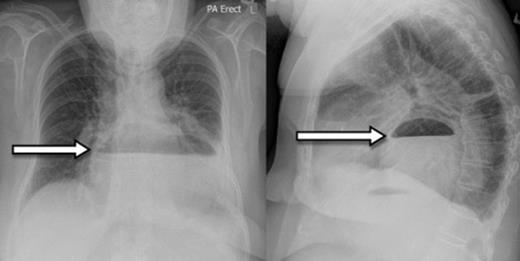

A 73-year-old Caucasian woman presented to the emergency department with 2-day history of vomiting and vague abdominal pain. Her background history included asymptomatic hiatus hernia, morbid obesity (BMI of 35.7), polymyalgia rheumatica, previous laparoscopic cholecystectomy, hypercholesterolaemia and hypertension. Regular medications included prednisone, amlodipine and cilazapril. On presentation she was tachycardic at 110 beats/min with otherwise normal vital signs. Her abdomen was generally tender but without any localised peritonism. Initial laboratory investigations on admission showed a leukocytosis (WCC of 13.8 x 109/L). Routine X-ray (figure 1) and subsequent (CT) scan (figure 2) both revealed a large strangulated paraoesophageal hernia. Radiographic changes (figure 3) were seen with gas within stomach wall, suggestive of gastric necrosis.

Chest X-ray showing paraoesophageal hernia with retro-cardiac air-fluid level (arrow)